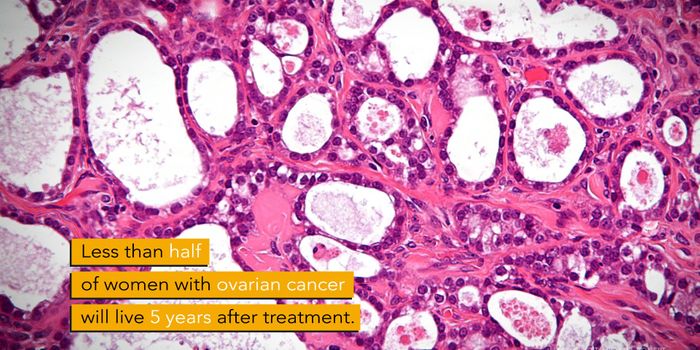

OCT 06, 2017VideosOctober is Breast Cancer Awareness Month; however, a recent study shows that many women are not aware of the issue of ov ...